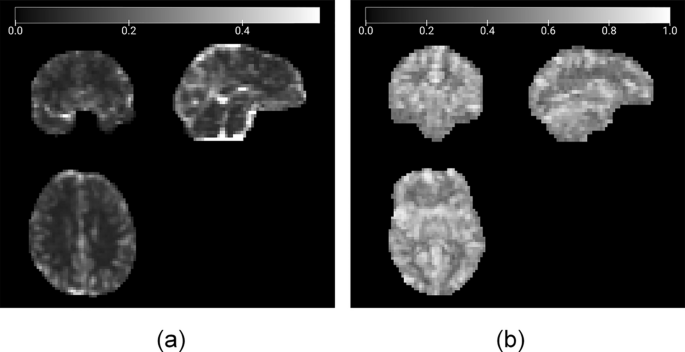

Power spectrum of the filtered time series was computed, and its square root was derived to obtain the amplitude across frequencies. ALFF was calculated by summing the power within the 0.01–0.08 Hz low-frequency band. fALFF was computed as the ratio of ALFF to the total power across all frequencies, providing a fractional metric to control for individual variations in signal strength. Examples of ALFF and fALFF maps are provided for an ASD participant in Fig. 2.

Amplitude of low-frequency fluctuations (ALFF)29 and fractional ALFF (fALFF)30 are maps generated to reflect resting-state fMRI spontaneous brain activity. ALFF and fALFF images are associated the underlying neuronal activity and metabolic processes in the brain30. Regions with higher ALFF or fALFF values are considered to be more “active” or engaged in intrinsic brain processes during the resting state30.